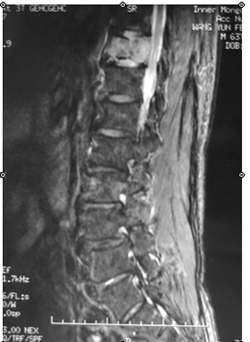

还有一个63岁的男性病人,也是因为腰背部疼痛下肢无力就诊于当地医院。检查发现T11椎体破坏。医生进行了透视下椎体肿瘤穿刺活检,但病理结果回报“正常的骨与骨髓组织,未见明显肿瘤细胞”。为了改善脊髓压迫,当地医生给病人实施了后路椎板切除及肿瘤部分切除减压和固定手术。术后病理回报为“平滑肌肉瘤”。术后半年肿瘤复发并进展。

图2-1,男性,63岁,T11椎体破坏,肿瘤累及椎管。

图2-2,术后半年MRI显示T11肿瘤复发且进展,椎管内的肿瘤对硬膜的压迫加重。